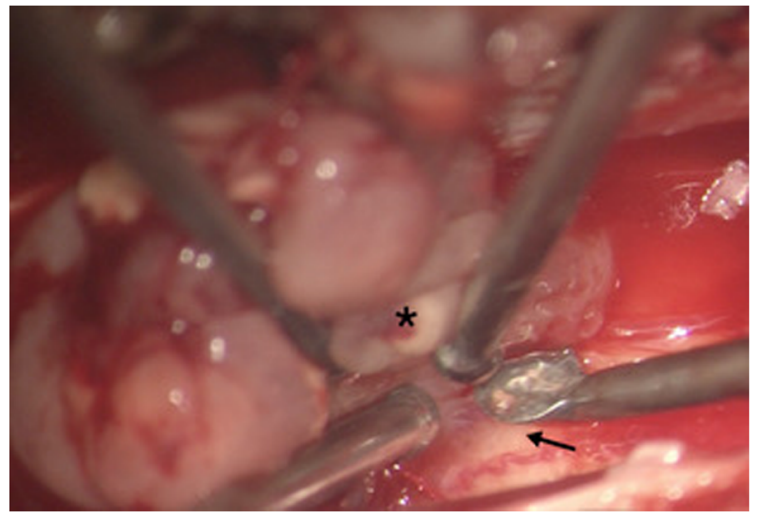

為進(jìn)行組織診斷,進(jìn)行了T7-T8椎板切除術(shù)以部分切除腫瘤。一旦病變被確定為毛細(xì)胞性星形細(xì)胞瘤,就繼續(xù)對(duì)腫瘤進(jìn)行切除。殘余腫瘤分兩個(gè)階段切除。在一開始手術(shù)中,從T4-T10行多層椎板切除術(shù)。在硬腦膜中線開孔后,發(fā)現(xiàn)腫瘤呈淺銀色附著在脊髓上(圖2)。我們進(jìn)行了細(xì)致的顯微手術(shù)切除,將腫瘤從脊髓中分離出來(lái)。腫瘤和脊髓之間有一個(gè)可識(shí)別的平面,這便于順利切除腫瘤,除了某些區(qū)域腫瘤似乎更粘連,并可能侵犯脊髓的pial覆蓋。在這些位置,腫瘤被從脊髓上切除,只留下一層薄的腫瘤。隨后,我們做了C4-T3椎板切除術(shù)來(lái)進(jìn)行二次切除和切除剩余的腫瘤。

圖2。術(shù)中圖像。術(shù)中圖像(放大5倍)顯示腫瘤(*),平面可識(shí)別,與正常脊髓容易分離(↑)